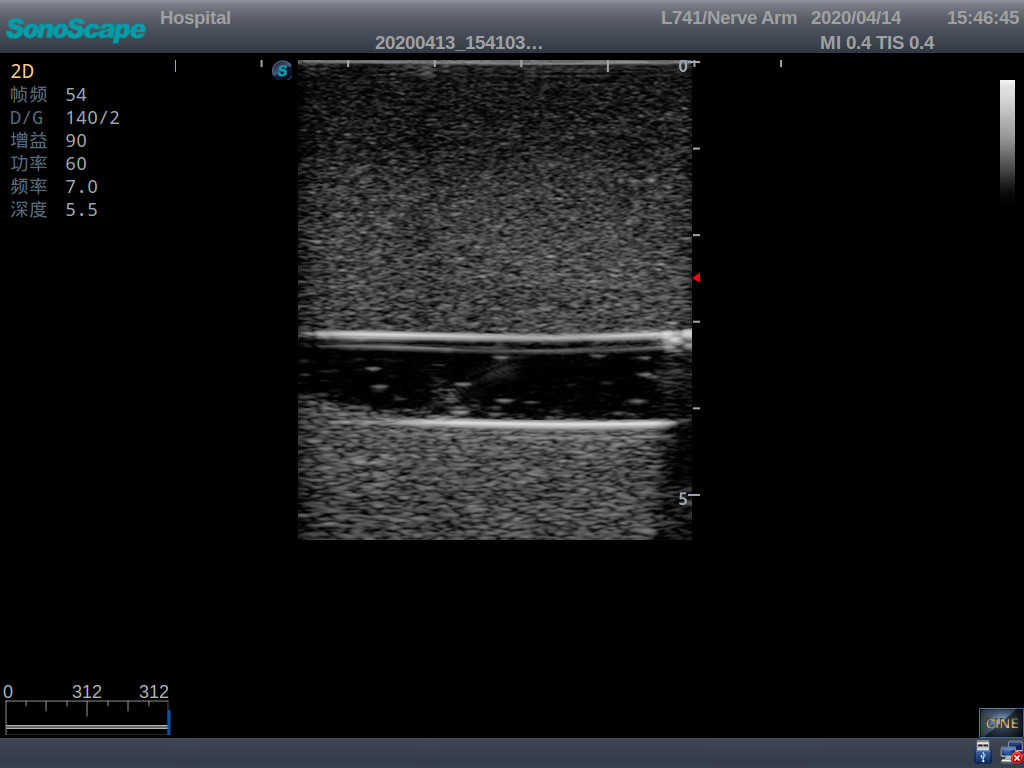

PICC Ultrasound Training Model

Model TYE1510.1

It is a model covering up from lobulus auriculae plane to the umbilical plane, and it has anatomical structures like clavicle, rib, sternocleidomastoid, jugular vein and basilic vein.

1)   Made of high molecular polymer ultrasound material, close to the real skin

2)   It can be used by real ultrasound machines

3)   Clear and real images of the tissues and organs (basilic vein and superior vena cava)